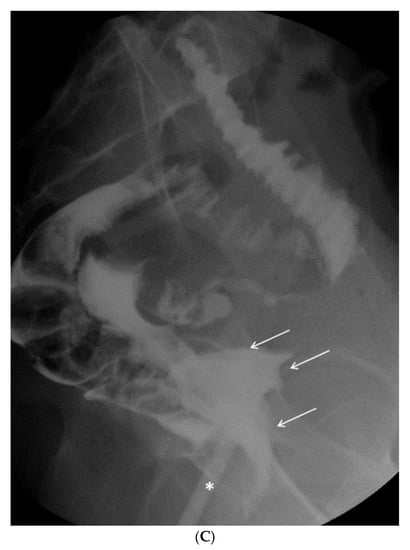

The radiologic tests confirmed the clinical suspicion of vagino-rectal fistula (Figure 7A–C), and the patient underwent adequate surgical treatment.

Figure 7.

(A) Plain radiography shows free subdiaphragmatic air (white arrows). (B) Contrast-enhanced CT. A small fistula (white arrow) connects the rectum with the upper portion of the vaginal canal. Diffuse thickening of soft tissues close to the mesorectal fascia is associated with a thin fluid layer (asterisks). (C) A frame of fluoroscopy obtained through single-contrast enema performed with gastrografin. The contrast medium, injected transvaginally through a small tube (asterisk), spreads into the surrounding soft tissues (white arrows) and, to a lesser amount, into the rectum (arrowhead), confirming the presence of a pervious fistula.